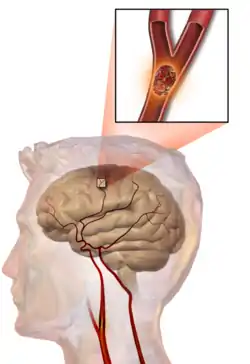

One of the top causes of death worldwide, strokes are disruptions of the blood supply to the brain. These disruptions can be triggered by a variety of ways, the most common of which are the rupturing of an artery (or hemorrhage), or blockages, which may either by from clots or other obstructions. Whatever the immediate cause, obstruction of the vascular system delivering blood to the brain can quickly lead to the death of cells in the affected areas. Like traumatic brain injury, the exact symptoms and consequences of a stroke depends on the region most affected, however there are some common characteristics. Paralysis or weakness on one side of the body- usually manifested in slurring of speech or drooping of the face- is very common since usually the blocked artery will be responsible for delivering blood to one specific brain hemisphere.

Several experimental therapies are being investigated or are already in place that address the challenges surrounding treating a patient who has experienced a stroke. Some are acute treatments aimed at clearing the obstruction in the arteries to get blood returning as quickly as possible and thus minimize cell death and the functional problems resulting from it, while others are rehabilitation regimens that try to restore lost capabilities. Although neuronal death can in many cases be slowed, there still does not exist any completely effective therapy for recovering lost brain areas in the case of severe strokes.